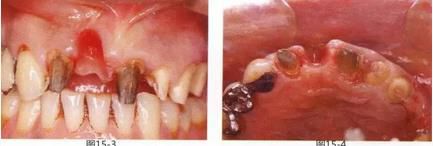

圖15-3  將橋冠拆除以后的正面照。橋體部牙齦由于炎癥而紅腫。

圖15-4  將橋冠拆除以后的咬合面照。橋體部的凹面較顯眼。